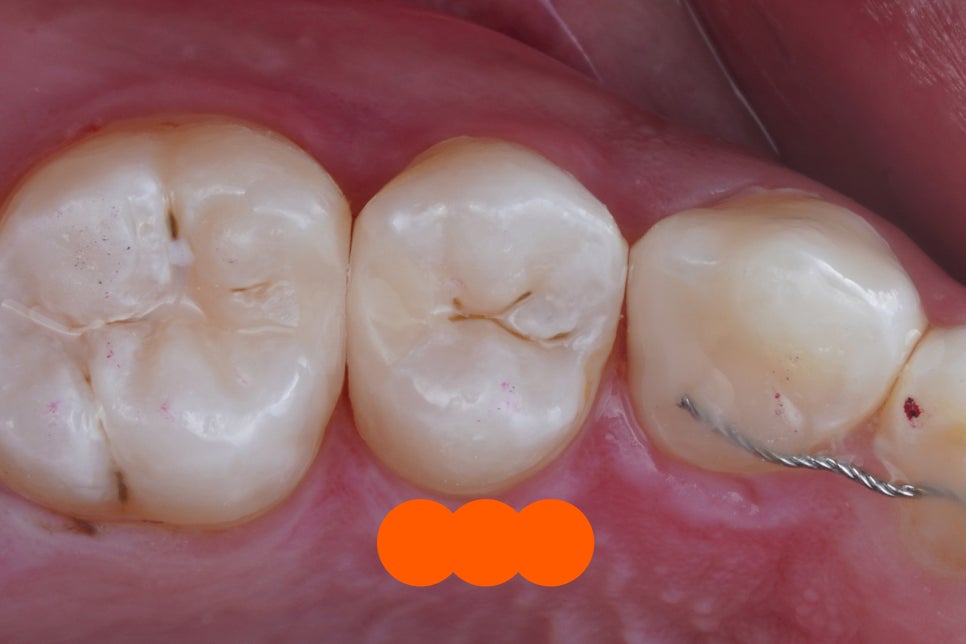

딱 봐도 충치가 굉장히 깊죠?

이렇게 충치가 깊은 경우

대부분 '신경치료'를 권유 받습니다.

이렇게 레진으로 치료가 가능하면

진단 자체를 굉장히 보수적으로 할 수 있습니다.

신경치료할 것도 레진으로 가능한 경우가 생기고

인레이는 말해 뭐합니까 레진으로 최소침습.

굉장한 장점이 되고 무기가 됩니다.

접착 술식 도중에는

이렇게 다양한 도구의 도움을 받아서

진료를 하게 됩니다.

충치 파내고 그냥 때우는 게 아니라,

적절한 재료를 사용해서

방습을 철저히 하고,

치아와 레진 사이에 턱이 지거나

빈공간이 생기지 않게끔

섬세한 작업이 필요합니다.

그래서 치료비도 일반적인 레진 비용과는 다르게

몇배, 많게는 10배 이상 차이나는 것이죠.

그래서 그냥 레진이 아니라

레진 빌드업 입니다.

어디를 때운건지 알 수 없을정도로

잘 되었네요.